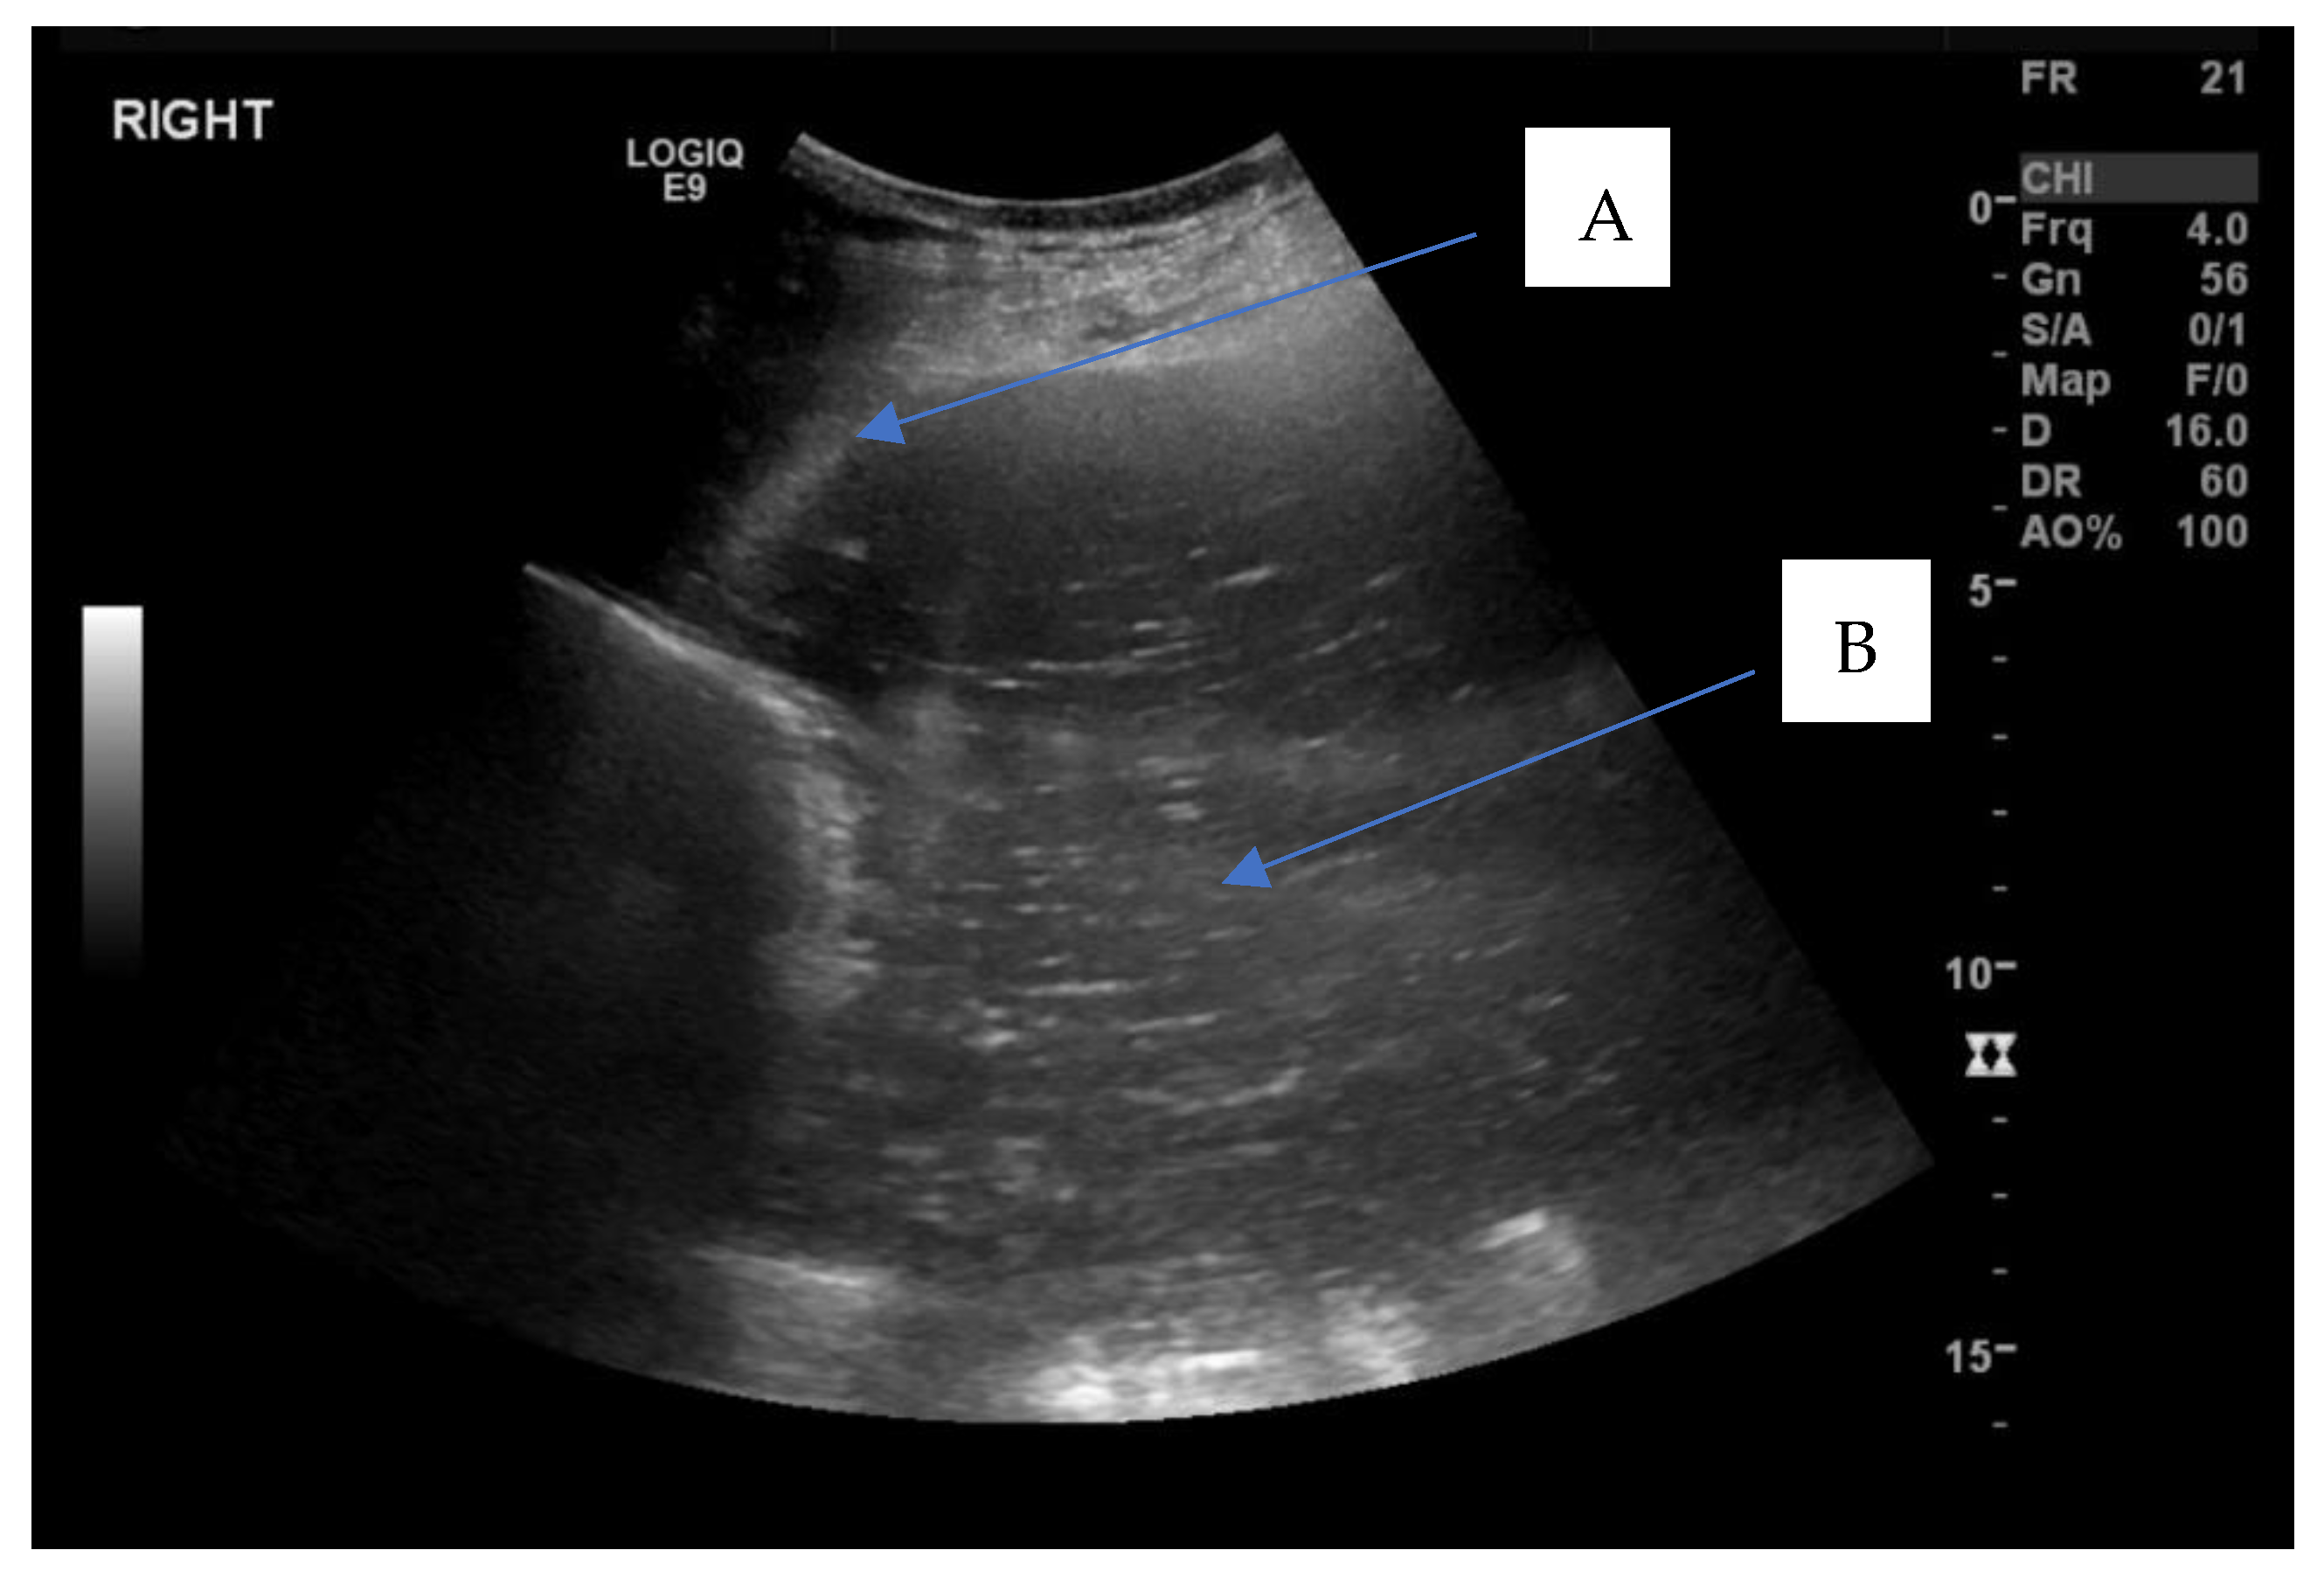

2.1. Presentation

2.2. Treatment